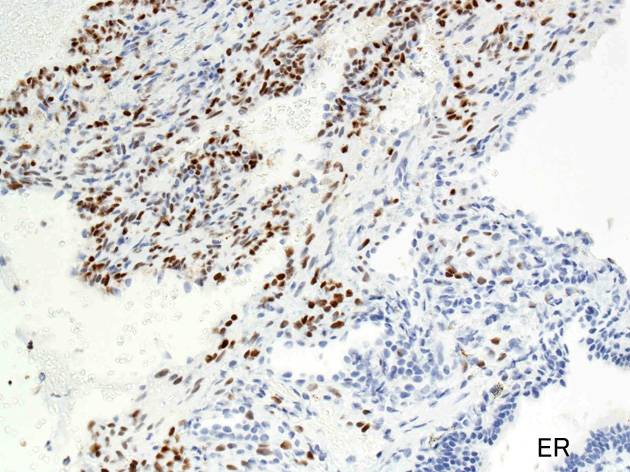

免疫染色

ER.jpg

PgR.jpg

Estrogen receptorProgesteron receptor